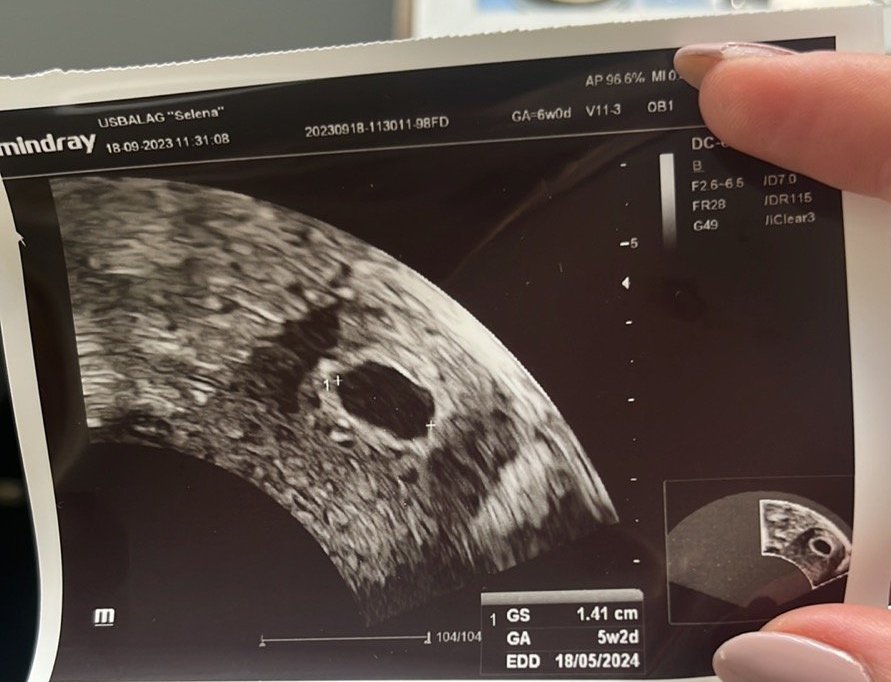

Първия ден на последната ми менструвация беше на 19.09.2023г. 4 положителни теста за бременност. Вччера беше първият ми преглед. Прикачам снимките от него. Видя се плоден сак с размер 18мм, ембрион не. Аз съм с две матки и плодния сак е в лявата матка. В левия яйчник имам и 40мм киста Sad . Притеснено ми е защо при тази големина на плодния сак не се видя ембрион. Преди 8 месеца претърпях куха беменност и се притеснявам изключително много да не се повтори. Чак след месец ще ми бъде следващия преглед, а до тогава ще се побъркам. Моля, ако някой може да помогне със съвет или е бил в подобна ситуация, да пише. Благодаря! Simple Smile

Може да се дължи на късна овулация. Но по принцип след 6г.с. може да се визуализира нещо (зависи и от техниката), Вие сте в 5+6 г.с. според снимката. Ако имате възможност отидете точно след седмица на преглед. Би трябвало всичко да е наред, стискам палци!